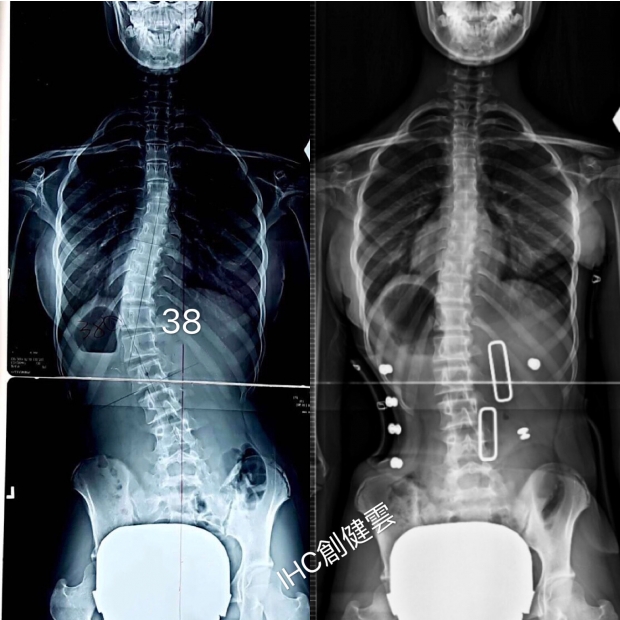

胸腰彎38度

14歲C型脊椎側彎女孩